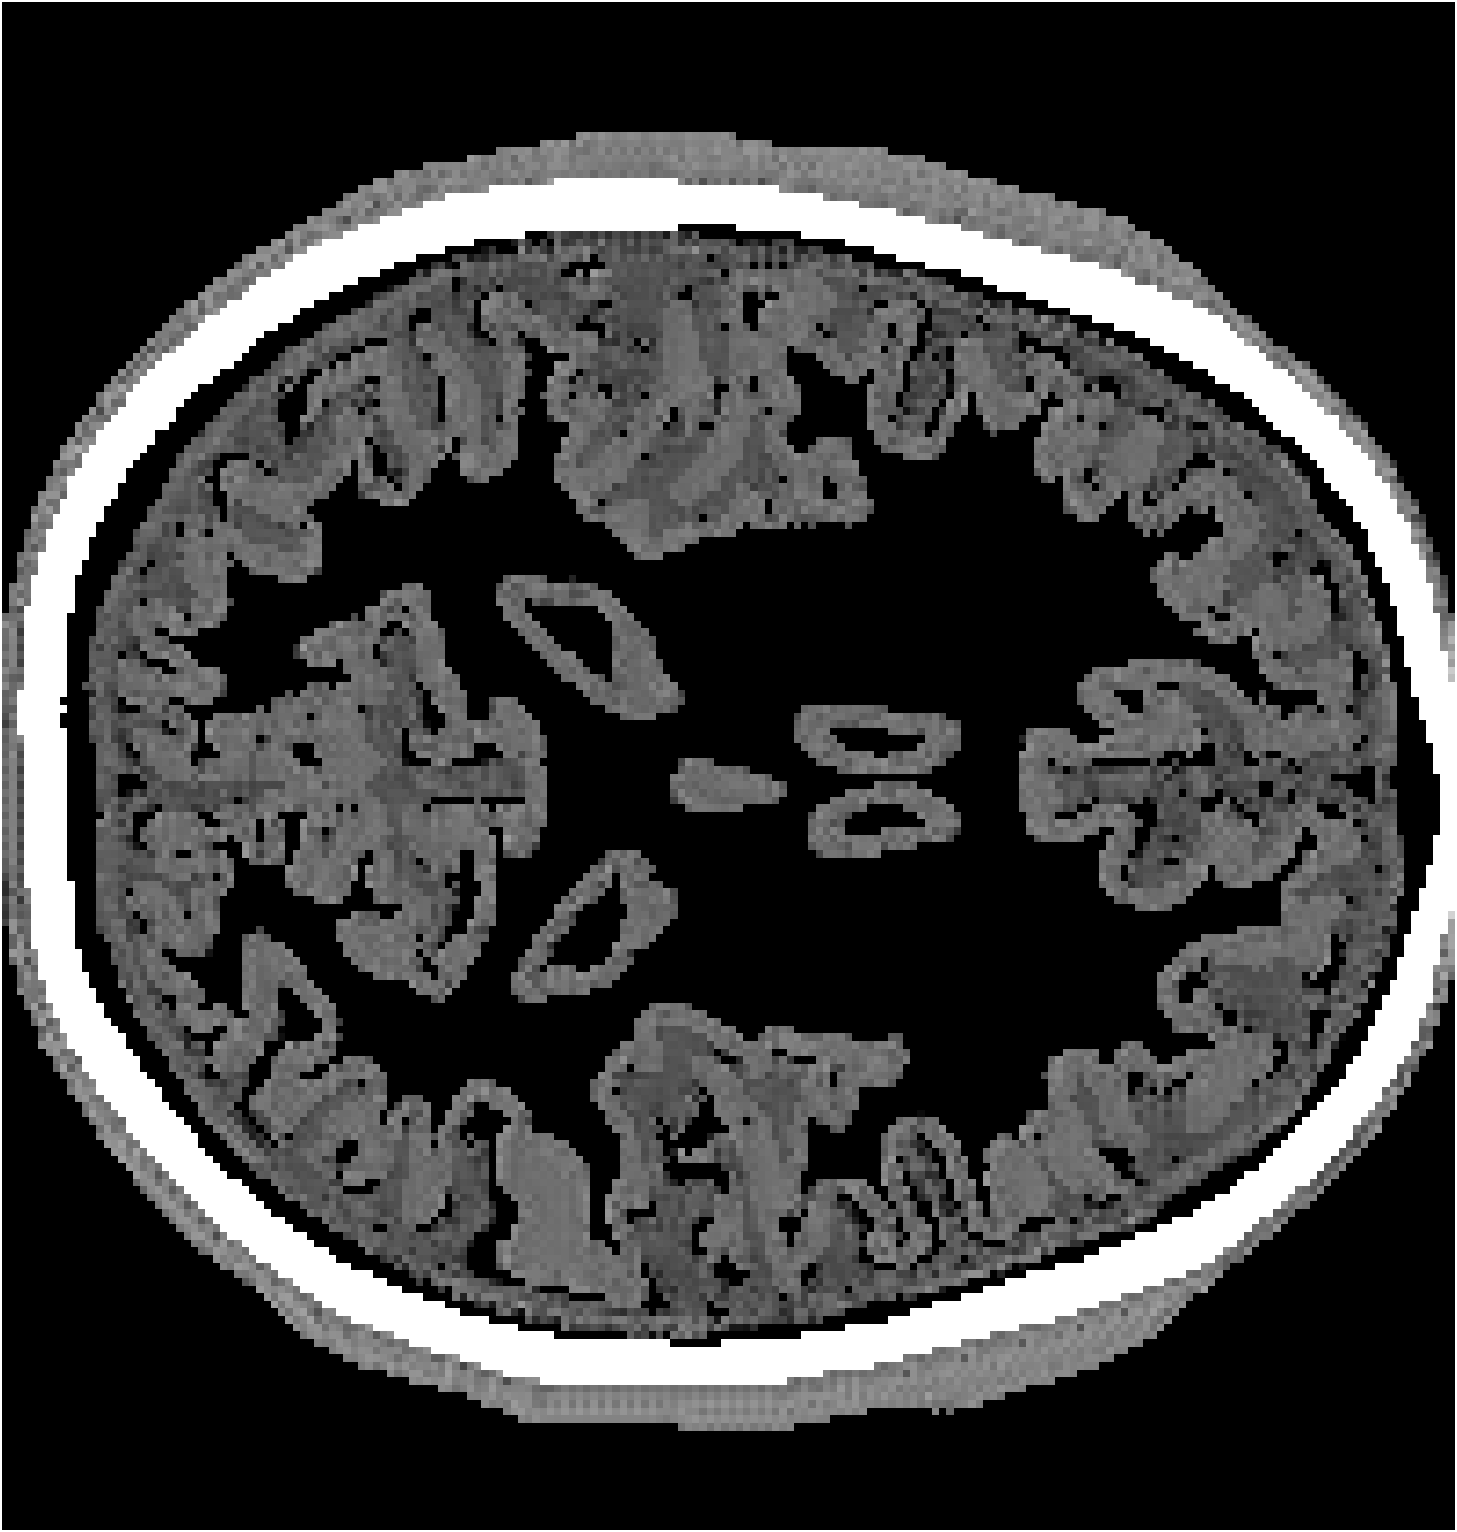

Refer to caption

(a) Partial-transducer dataset

Figure 7: Stacked TRA Image with (a) Partial-transducer dataset and (b) Full-transducer dataset

To evaluate performance, we construct two acquisition setups using the same horizontal 2D slice of the phantom: (i) an idealized full-transducer dataset (Figure 3(b)) providing near-uniform coverage along the head contour, and (ii) a partial-transducer dataset (Figure 6) designed to reflect practical acquisition constraints. In the partial setup, a linear array with 51-element is repositioned around the head; for each view, the central element transmits and all other 50 elements receive. The partial setup includes 50 sweeps covering the full 360, meaning that for each sweep, the source and receivers rotate by 360/50=7.2360/50=7.2^{\circ}. Sweeping 50 views yields, per 2D slice, a channel tensor of shape (T,Ns,Nr)=(5001,50,50)(T,N_{s},N_{r})=(5001,50,50). The key distinction between these two datasets is their aperture: full-transducer provides near 360 coverage in a single placement, whereas partial-transducer attains coverage by aggregating neastest 50 receivers in a single placement, which is only around 36. Particularly, the partial-transducer setup includes only 50 sweeps, while the full-transducer setup uses all receivers covering the entire brain, with each transducer acting as a source in turn while the others serve as receivers. Compared to the full-transducer, the partial-transducer achieves coverage by combining a much smaller number of views. For each sweep, we generate the forward wavefield g(𝐱,t|𝐠){{g}}(\mathbf{x},t|\mathbf{g}) and the back-propagated wavefield p~(𝐱,t|𝐠)\tilde{{p}}(\mathbf{x},t|\mathbf{g}) and generate the TRA fragment with Eq. (7) (example in Figure 6). With the physical TRA method, the TRA fragment can be stacked to give the stacked TRA image. To validate the differences between the two datasets, we generated stacked TRA images using both datasets, as shown in Figure 7. As shown in Figure 7(b), the full-transducer dataset provides significantly greater detail in internal structures. Despite higher levels of noise and artifacts caused by the limited number of views, the partial-transducer dataset is still capable of capturing some meaningful tissue structures.